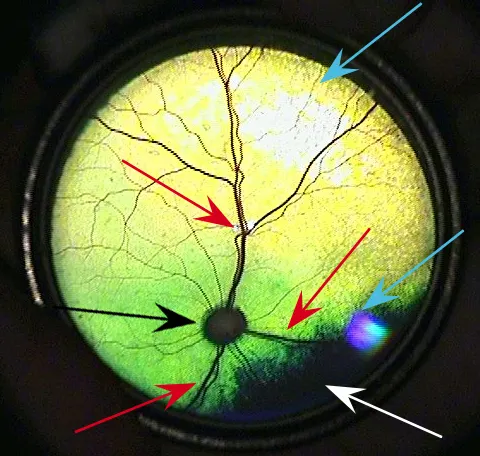

FIGURE 1

Normal feline fundus. Typical appearance of the holangiotic pattern of the feline fundus in an 8-year-old castrated domestic short-haired cat. The retinal vasculature has three pairs of cilioretinal arteries (red arrows). The nontapetum is also present at the inferior aspect of the fundus (white arrow) and is usually very dark brown. The optic nerve (black arrow) is typically located in the tapetum, is nonmyelinated, and is gray to dark gray.1 Flash artifacts are present in both the superior and inferior aspects of the image (blue arrows).